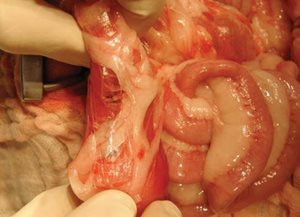

Photo 3

De part et d’autre du corps étranger, l’intestin est occlus pour éviter toute fuite de son contenu lors de l’entérotomie.

Idéalement, cette occlusion est réalisée par un assistant qui clampe l’intestin entre son index et son majeur (Cela évite une pression excessive entre le pouce et l’index).

Si aucun assistant n’est présent, l’occlusion peut être réalisée avec des pinces de Doyen.